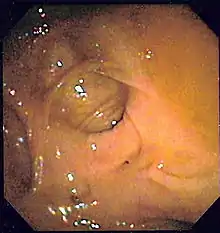

- يُظهر تنظير القولون الرتوج ويستبعد الورم الخبيث. يجب عمل فحص القولون بالمنظار بعد 4-6 أسابيع من النوبات الحادة.